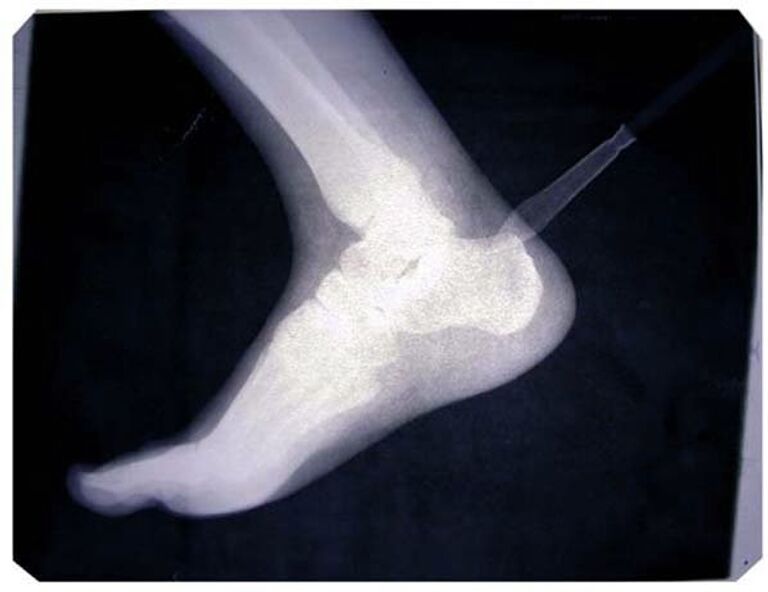

3. Имя художника Василия Слонова в последнее время чаще всего звучит в связи со скандальным увольнением Марата Гельмана из Пермского музея современного искусства PERMM — все это произошло ровно после открытия выставки Слонова "Welcome! Sochi 2014" в рамках фестиваля "Белые ночи". В Москве о Сочи больше ни слова: художник представляет на Винзаводе свой давний проект "Друзья детства". Это рентгеновские снимки литературных героев из детства автора – Карлсона, Раскольникова, Гамлета, Буратино и многих других, которые помогают ему мириться с суровой действительностью.

В Галерее 11.12 на Винзаводе с 7 ноября по 8 декабря